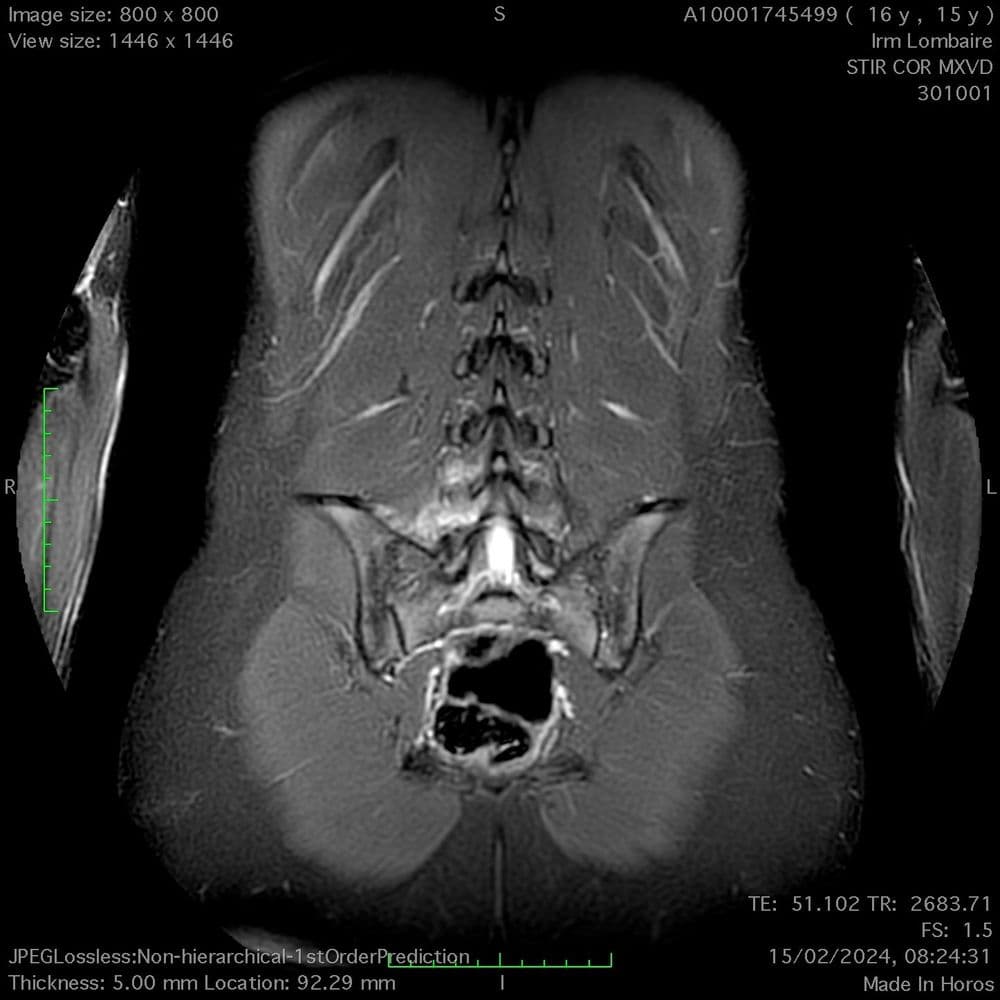

Claudication radiculaire bilatérale d'apparition progressive chez une patiente de 65 ans.

MRI